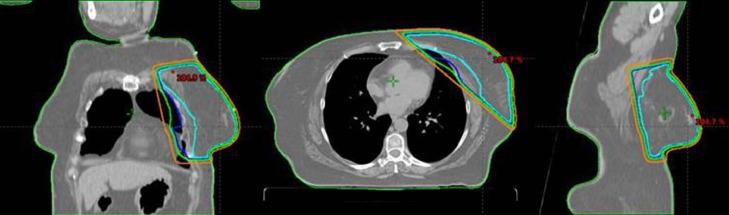

Preoperative Accelerated Hyperfractionated Whole-Breast Radiation as Treatment for Secondary Angiosarcoma of the Breast After Prior Accelerated Hypofractionated Whole-Breast Radiation Therapy: A Case Report and Review of the Literature.

Adv Radiat Oncol. 2022 Jan 19;7(4):100846. doi: 10.1016/j.adro.2021.100846. eCollection 2022 Jul-Aug.

DOI:10.1016/j.adro.2021.100846

PMID:35243183

原文链接:https://pmc.ncbi.nlm.nih.gov/articles/PMC8866668/